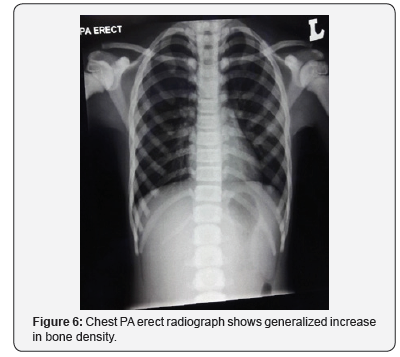

On examination, her height is at the fiftieth centile. There are no abnormal facies, no cranial anomalies, no frontal bossing, no hydrocephalus, no abnormal eye moments/ nystagmus. No bruises, purpura and no pallor seen. Abdominal examination reveals no hepatosplenomegaly. Her hemoglobin was 10.5 (low), hematocrit 34, WBC 6.13 and platelets 381. Serum calcium and phosphate levels were normal, alkaline phosphatase elevated. Plain radiographs reveal rugger- jersey appearance of her spine (Figure 4), “end bones” seen within her pelvis (Figure 5) and chest radiograph shows generalized increase in bone density (Figure 6).